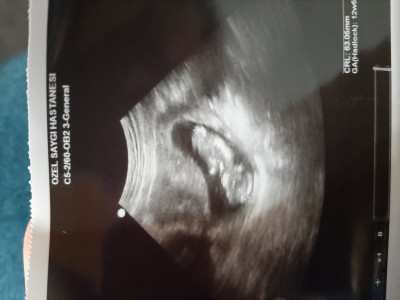

Doktorumuz %60 bi tahminde bulundu birde siz bulunun Bakalim hanimlar yorum yapan herkese tesekkur ederim

12+5